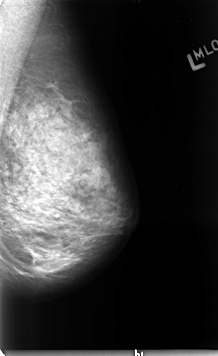

B_3079_1.LEFT_MLO

LEFT_MLO LINES 4624 PIXELS_PER_LINE 2832 BITS_PER_PIXEL 12 RESOLUTION 50 NON_OVERLAY